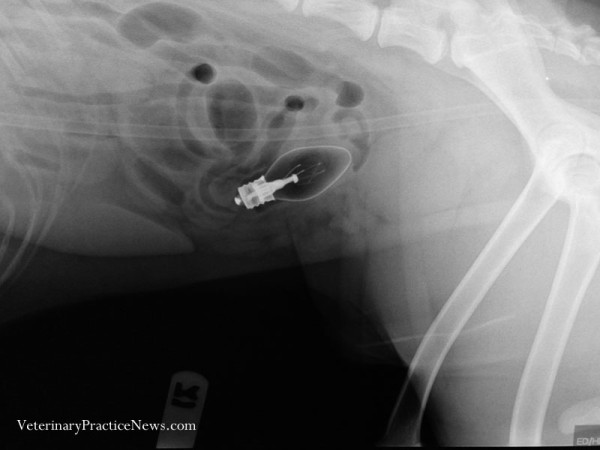

Baseado na avaliação física e radiografia, o veterinário conseguirá dizer se o objeto vai sair “naturalmente” (através das fezes) ou se será necessário fazer uma cirurgia para remoção.